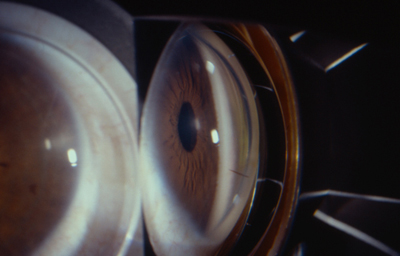

Fotos 1 - Picadura en el Limbo temporal

Postoperatorio con edema de córnea que fue cediendo progresivamente. - Polo posterior sin alteraciones.- Tensión Ocular 12 aplanático de Goldman

A los 5 meses: Refracción: AVsc 1.00 +0.50 esférico AVcc 1.00. Discreto engrosamiento corneal en creciente, inferior-temporal. - Despigmentación del Iris, pupila normoreactiva. Tensión ocular 12 aplanático de Goldman.

Último control a los 24 meses. Refracción: AVsc 1.00 +0.75 esférico AVcc 1.00. Subjetivamente Bien. - Creciente corneal inferior engrosado con mayor textura en la Descemet. (Foto No2)

Foto 2 - Ultimo control a los 24 meses